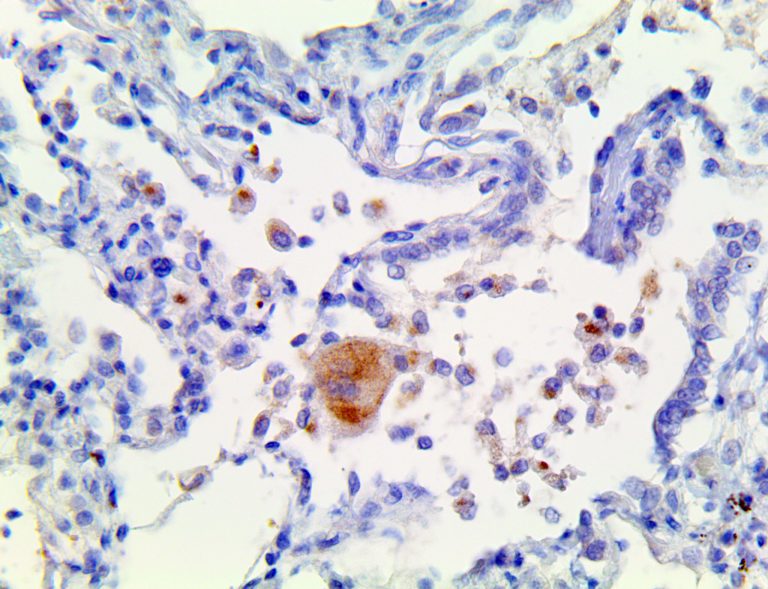

It is the ICU physician who is most likely to witness one of the deadliest manifestations of the abnormal immunological response, the cytokine storm syndrome (CSS). This response is also referred to by some as the cytokine release syndrome (CRS). CSS is characterized by continuous activation and expansion of macrophage and lymphocyte populations, which secrete large amounts of cytokines, causing the cytokine storm. This massive cytokine release is akin to hemophagocytic lymphohistiocytosis (HLH) disease, a syndrome characterized by initial unchecked and persistent activation of cytotoxic T lymphocytes and NK cells.

Clinical and laboratory manifestations of HLH include fever, enlarged liver and/or spleen, neurologic dysfunction, coagulopathy, liver dysfunction, cytopenias (i.e., low levels of erythrocytes, leukocytes, and/or platelets), hypertriglyceridemia, hyperferritinemia, hemophagocytosis, and eventually diminished NK cell activity as the immune system becomes progressively paralyzed. HLH can be familial (primary HLH) or secondary to another disease process (sHLH), such as rheumatic disease, in which it is referred to as macrophage activation syndrome (MAS, characterized by elevated ferritin).